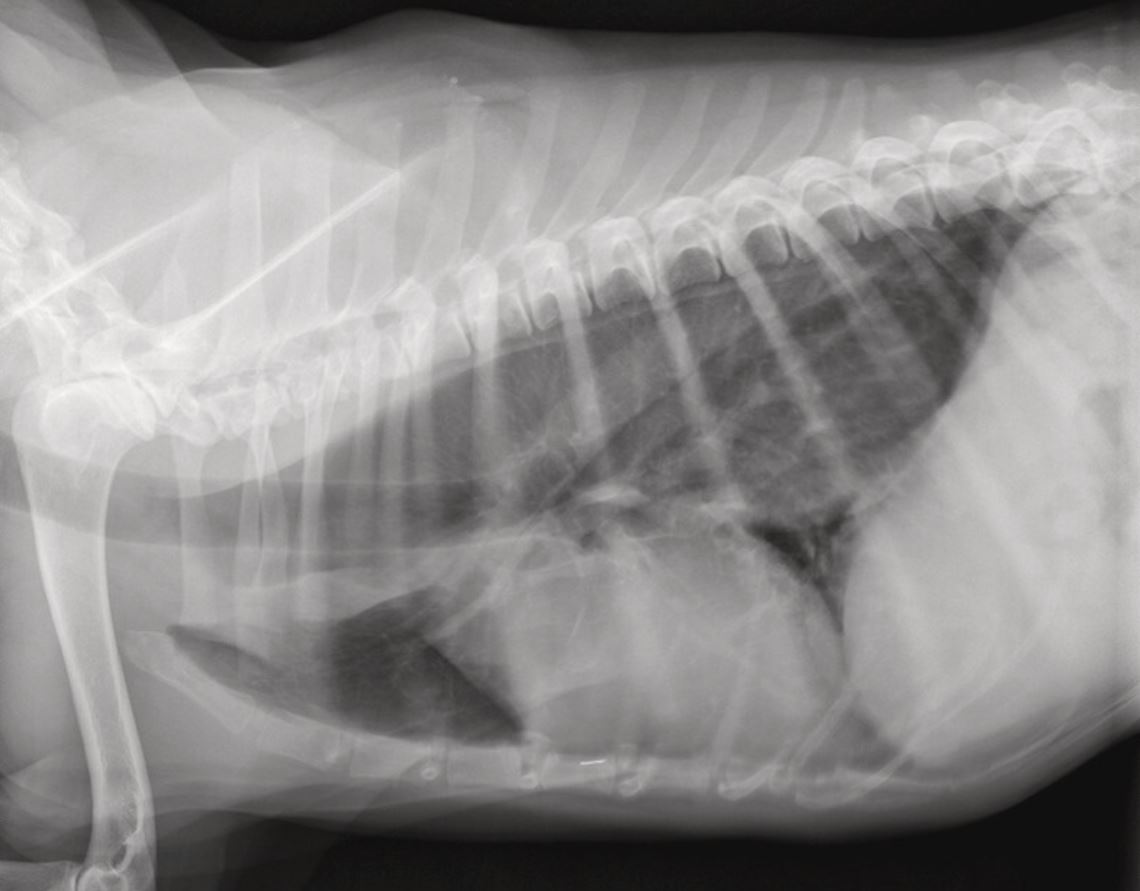

Verdacht auf Megaösophagus oder Divertikel

Ein Megaösophagus oder Divertikel im Rahmen einer Rechtsaorta kann durch ein Röntgenbild vom Thorax diagnostiziert werden [Abb. 5]. Im ersteren Fall sollten Endokrinopathien (Hypoadrekortizismus, Hypothyreose) sowie eine Myasthenia gravis (über die Acetylcholin-Rezeptor-Antikörper-Bestimmung) ausgeschlossen werden.